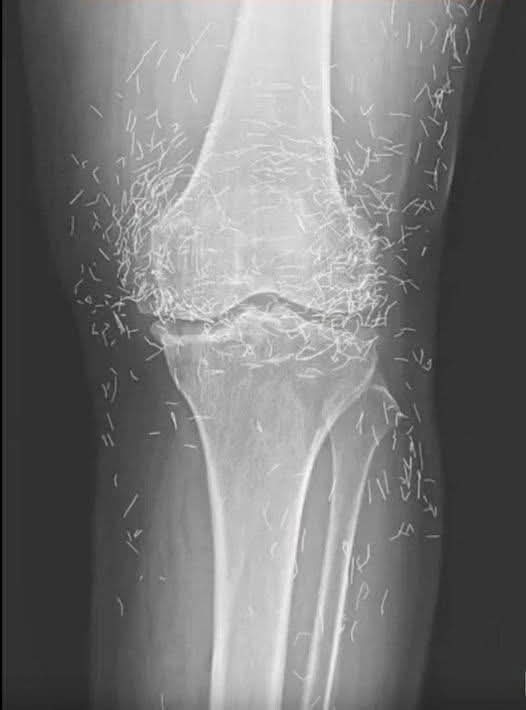

🩺 患者は膝の激しい痛み、腫れ、可動域制限を訴えて病院を受診しました。 医師は身体診察後、原因究明のため患部のX線検査を指示しました。 画像には何が写っていますか? 診断は何ですか?